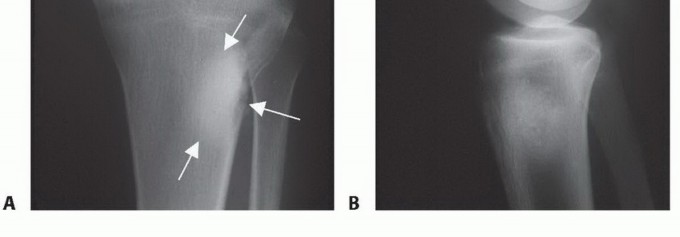

- الأشعة السينية (X-rays): هي الخطوة الأولى، وتُظهر التغيرات في بنية العظم، مثل التدمير العظمي، أو تكوين العظم الجديد، أو رد فعل السمحاق.

- الساركوما العظمية (Osteosarcoma): هو أكثر أنواع سرطان العظام الأولية شيوعاً، وغالباً ما يصيب الشباب والمراهقين. يتميز بسرعة النمو وقدرته على الانتشار (النقائل) إلى أجزاء أخرى من الجسم، خاصة الرئتين.

- ورم الخلايا العملاقة (Giant Cell Tumor - GCT): يُعد من الأورام الحميدة ولكنه قد يكون عدوانياً محلياً، ويمكن أن يُسبب تدميراً كبيراً للعظم وقد يتكرر بعد الاستئصال. في حالات نادرة جداً، قد يتحول إلى ورم خبيث.